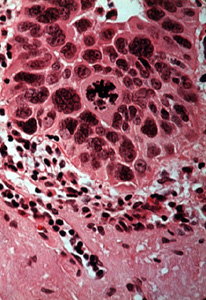

| Una vista a más aumentos muestra las anormalidades celulares similares a aquéllas

descriptas en el displasia de la mucosa, dilatación vascular y degeneración del colágeno

extensa ("elastosis senil"). Éstas son las alteraciones debido a la radiación solar. |